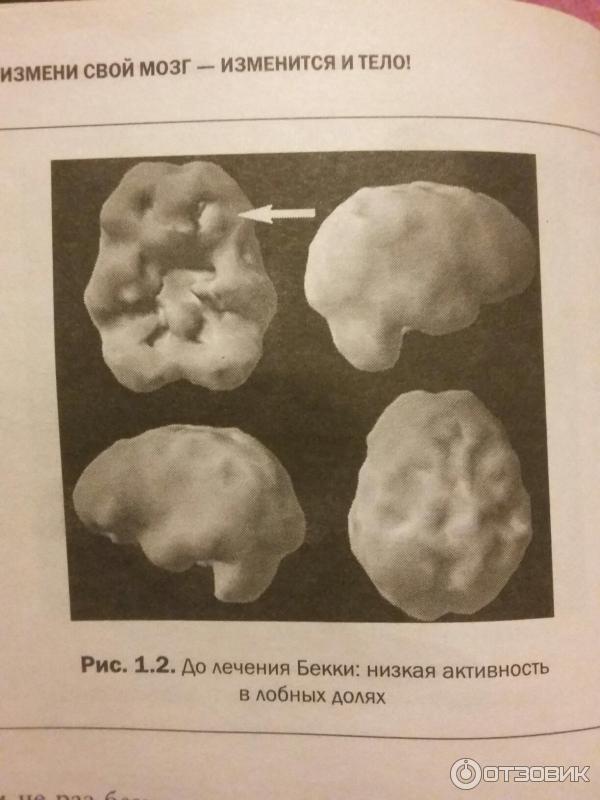

Технологии будущего: Замена мозга

Раздел: Житейские мотивы